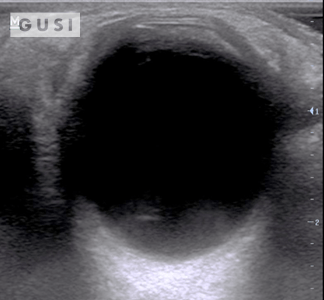

During the 2017 World Taekwondo Championships in Muju, Korea, a 30-year-old female athlete from Hong Kong was kicked in her left eye by an opponent. She reported fluctuating vision accompanied by pain during eye movement. A POCUS examination of the affected eye indicated a vitreous hemorrhage, with no evidence of lens subluxation or globe rupture.

On the ultrasound, as the athlete moved her eyes laterally, the hemorrhage (denoted by a white arrow) exhibited a swirling pattern within the globe, consistent with her eye movement. The athlete was promptly referred to a specialized medical center for an ophthalmology consultation, where the diagnosis of vitreous hemorrhage was confirmed. The patient was subsequently discharged from the Emergency Department with specific precautionary measures.